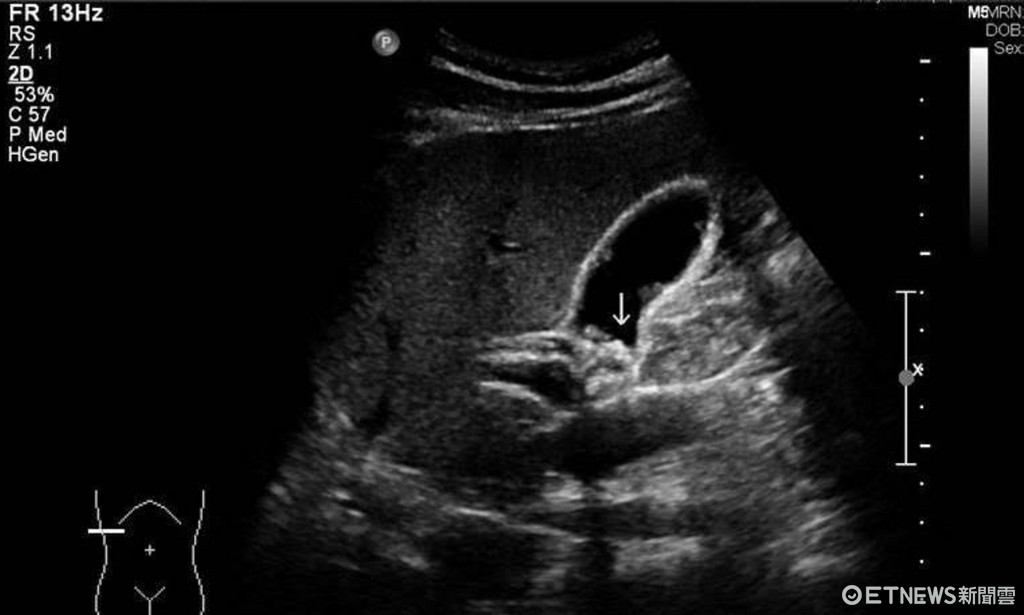

▼膽結石超音波照。(示意圖/書田診所提供)

南投醫院外科李博彰主任表示,蔣婦膽管結石合併阻塞性黃疸,正常的膽管大小不到0.5公分,但她的膽管已被結石堵住而腫脹擴大超過2公分,因為結石阻塞膽管,膽汁排不出,便造成黃疸,若不立即處理,可能會引發敗血症,有生命危險,並說明膽囊被摘除後,肝臟仍繼續分泌膽汁,若仍持續暴飲暴食或其他因素,還是有可能產生膽管結石,不能輕忽。